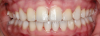

Fig 4. A 15-year postoperative photograph of the patient in Fig 3 illustrates the significant infraocclusion of the implants compared to the natural teeth. Also, note the blue tissue discoloration over implants Nos. 7 and 11.

A third risk of using an implant to replace a missing lateral incisor is the continued vertical growth of the alveolar bone and eruption of the teeth adjacent to the implant.9,10 Traditionally, it has been taught that an implant can be safely placed when alveolar bone growth is confirmed complete with serial radiographs. However, numerous studies call that rule into question.11-16 Bernard et al evaluated vertical changes in teeth adjacent to implants in a young group of patients (15.5 to 21 years) and in a mature group (40 to 55 years), over a mean time of 4.2 years.17 In the young group, infraocclusion of the implant crowns ranged from 0.1 mm to 1.65 mm, while in the mature group the infraocclusion of the implant crowns ranged from 0.12 mm to 1.86 mm. An example of infraocclusion that occurred in a young implant patient over time is depicted in Figure 3 and Figure 4. Based on classic literature as cited here, it seems prudent to delay the placement of implants in high-risk areas, such as the maxillary lateral incisor region, for as long as possible or perhaps avoid it altogether.